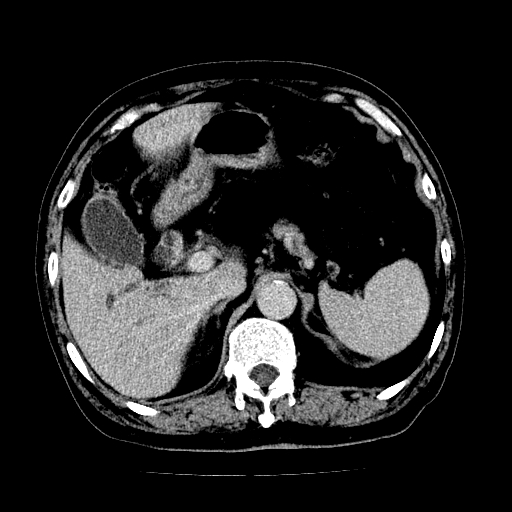

男,71岁,皮肤黄染四天。

肝内外胆管及胆总管上段扩张,考虑为梗阻所致,建议mrcp检查。

考虑胆总管癌并肝内外胆管扩张。

胆管癌并肝内外胆管扩张。

支持考虑胆总管癌并肝内外胆管扩张。 局部应薄扫。心包钙化。

胰腺上端胆总管内见软组织影,强化不明显,结合临床,还是考虑低位梗阻性黄疸,胆总管癌可能性大